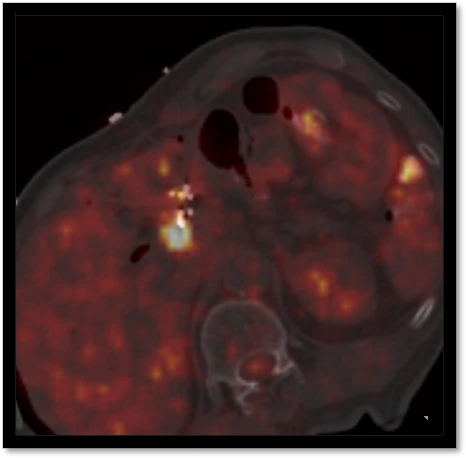

肿瘤微创治疗之所以微创就是对病灶实施精确打击,PET/CT好比相控阵雷达,可以清晰分辨异常和正常组织

PET/CT在融合CT图像后可以完成术中增强扫描,避开危险血管

传统CT依靠病灶密度来判定疾病,很多疾病当出现形态学改变就已经“晚了”

传统CT引导对肺组织等密度差异较大组织有一定优势,但是对肺不张无能为力